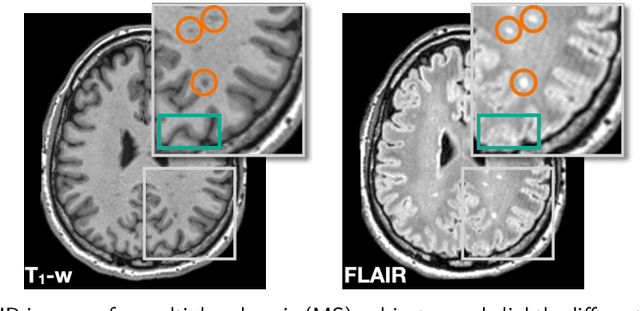

Abstract:The lack of standardization is a prominent issue in magnetic resonance (MR) imaging. This often causes undesired contrast variations due to differences in hardware and acquisition parameters. In recent years, MR harmonization using image synthesis with disentanglement has been proposed to compensate for the undesired contrast variations. Despite the success of existing methods, we argue that three major improvements can be made. First, most existing methods are built upon the assumption that multi-contrast MR images of the same subject share the same anatomy. This assumption is questionable since different MR contrasts are specialized to highlight different anatomical features. Second, these methods often require a fixed set of MR contrasts for training (e.g., both Tw-weighted and T2-weighted images must be available), which limits their applicability. Third, existing methods generally are sensitive to imaging artifacts. In this paper, we present a novel approach, Harmonization with Attention-based Contrast, Anatomy, and Artifact Awareness (HACA3), to address these three issues. We first propose an anatomy fusion module that enables HACA3 to respect the anatomical differences between MR contrasts. HACA3 is also robust to imaging artifacts and can be trained and applied to any set of MR contrasts. Experiments show that HACA3 achieves state-of-the-art performance under multiple image quality metrics. We also demonstrate the applicability of HACA3 on downstream tasks with diverse MR datasets acquired from 21 sites with different field strengths, scanner platforms, and acquisition protocols.